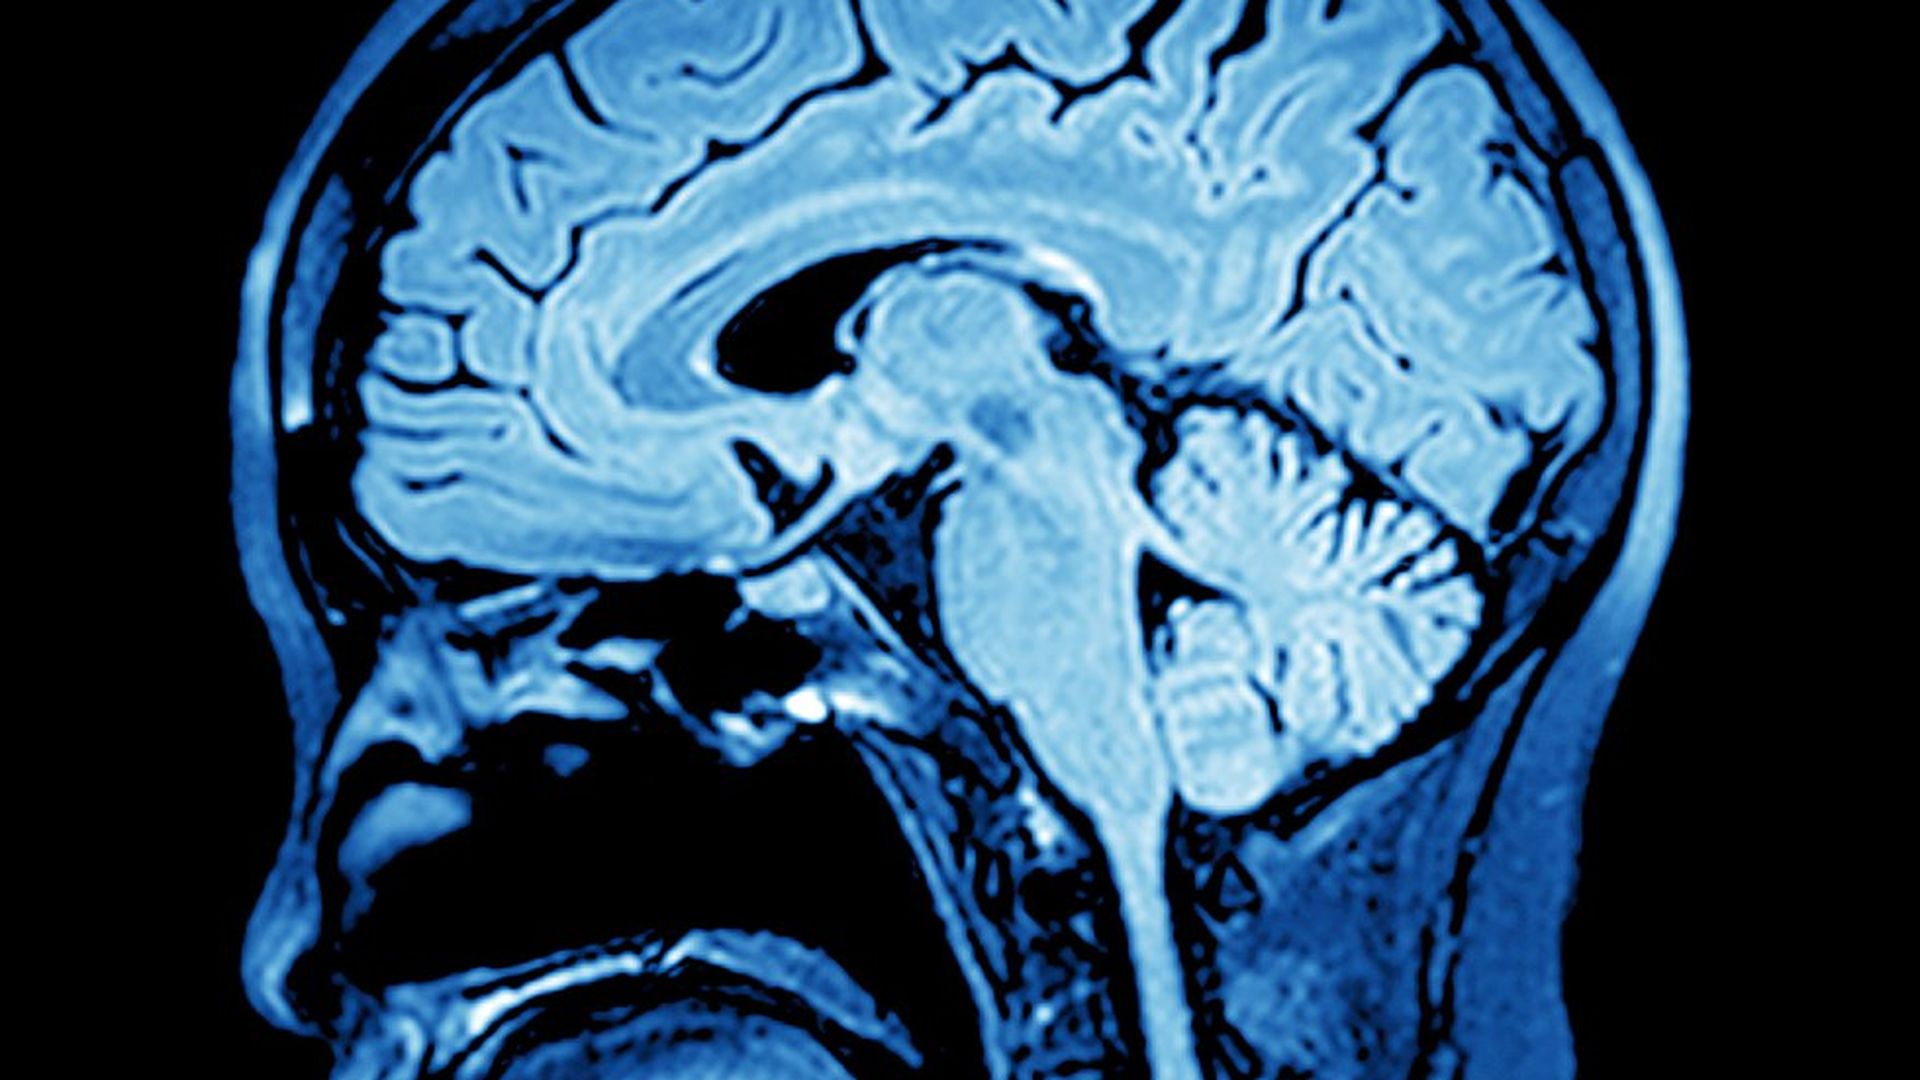

Traumatic brain injuries may increase risk of dementia

A nationwide study of traumatic brain injuries (TBI) in Finland has found that being hospitalized with a moderate to severe TBI as an adult increases the risk of dementia later in life.